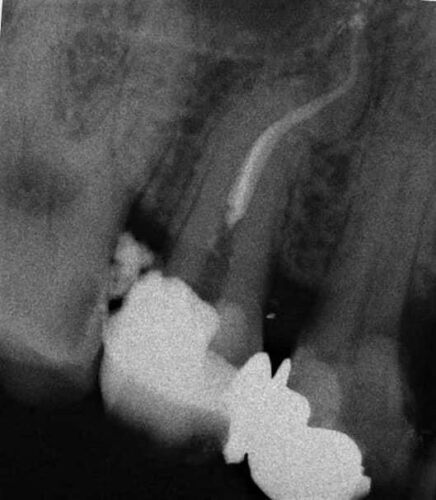

Il caso di questo 1.5 è stato affrontato con il sistema Mtwo usato manualmente.

1.5 RX intraoperatoria

P.Sl. La rx intraoperatoria mostra il 25-06 in apice.